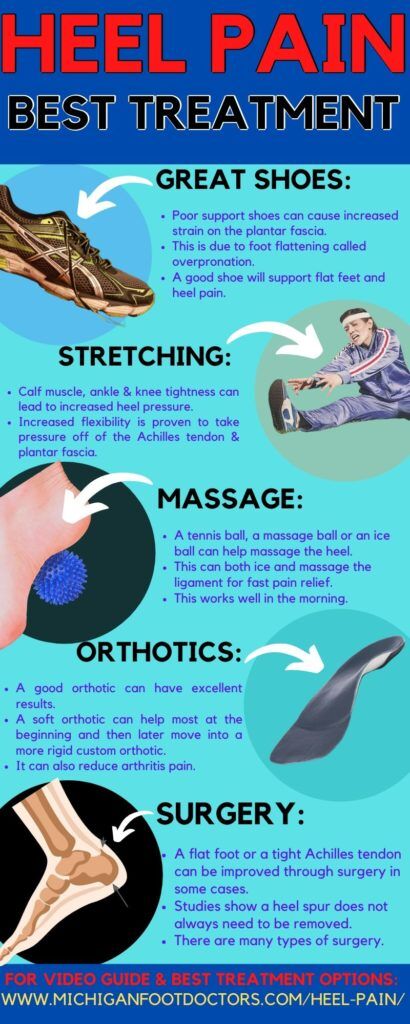

Plantar Fasciitis Treatment Symptoms Causes Prevention PediFix

Mid Foot Pain Causes Symptoms Best Home Treatment

Flat Feet Pain Treatment Hyperhealth

Flat Feet Causes Symptoms Treatment Brisbane Physiotherapy